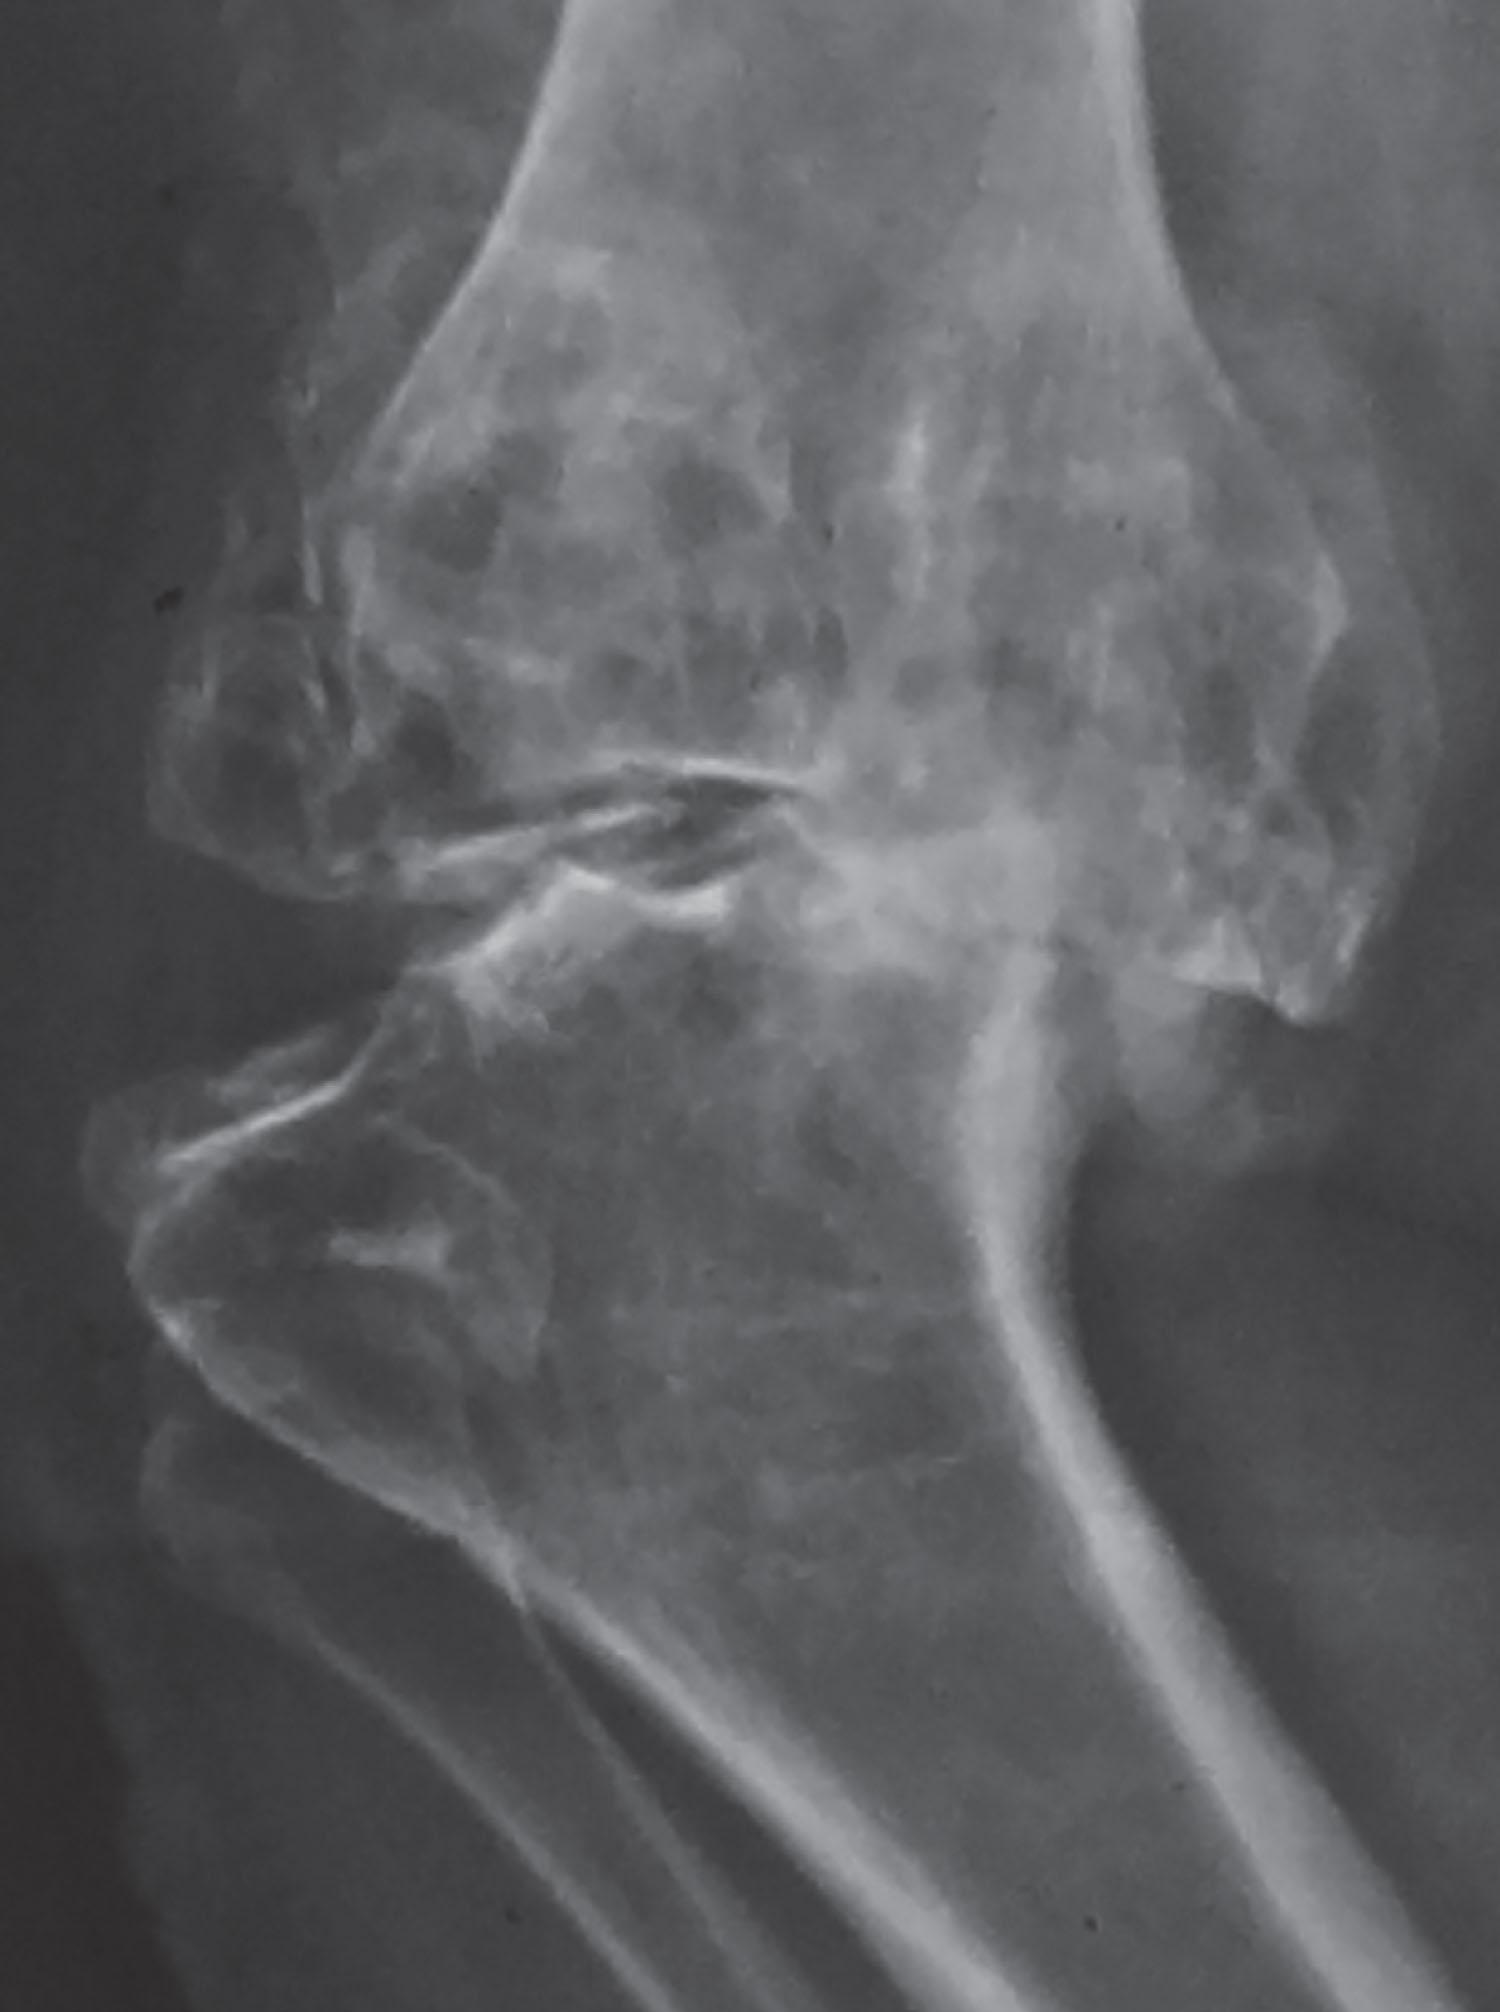

• Reactive bone remodeling should be sought on the radiograph. Its presence denotes significant deformity and the possibility that reduction osteotomy may be deployed to balance gaps ( Fig. 9.12 ).

Fig. 9.12, Radiograph displays marked posteromedial reactive bone remodeling.